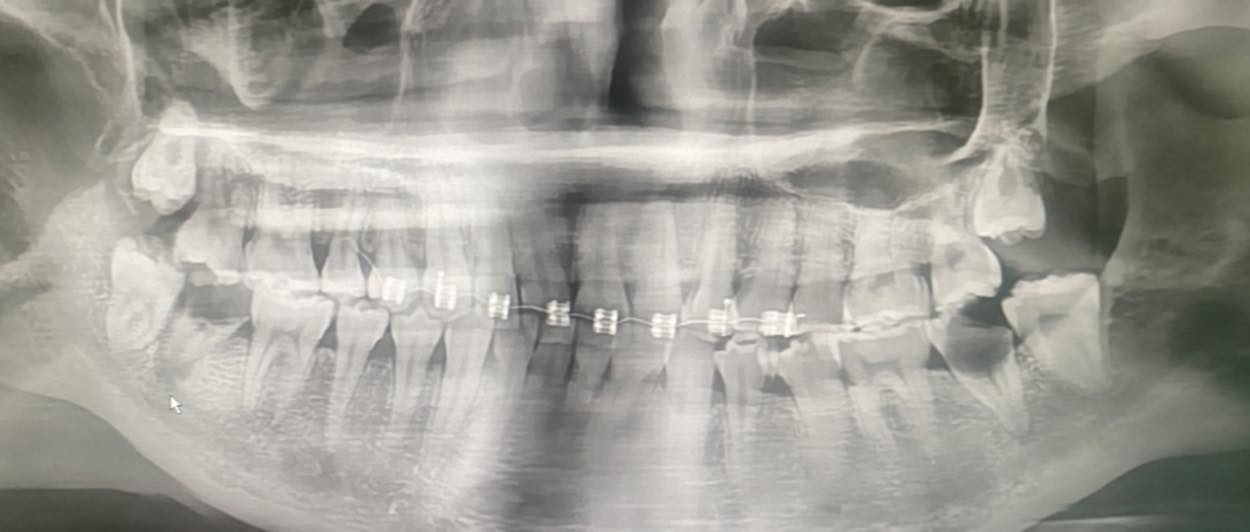

เคสจริงที่หมอเจอ น้องอายุเพียง 20 ปี

เริ่มจากจัดฟันแฟชั่นในกรุงเทพฯ → ฟันผุ มีหนอง→ เชื้อเข้ากระแสเลือด → จับเชื้อ Streptococcus gordonii→ กลายเป็น เยื่อบุหัวใจติดเชื้อ (Infective Endocarditis)

สุดท้ายลิ้นหัวใจรั่ว ต้อง ผ่าตัดเปลี่ยนลิ้นหัวใจ ทั้งที่ยังอายุน้อยมาก ทั้งหมดนี้ เริ่มต้นแค่เพราะ “อยากจัดฟันแฟชั่น”

จัดฟันแฟชั่นทำมาจาก กทม. สัก 6 เดือนที่แล้ว ไอ หายใจไม่ค่อยสะดวก โทรหาแม่ แม่เลยพามารักษาที่น่าน อายุ 20 ปี แม่ให้ลาออกจากงานมารักษาตัวให้หายก่อน